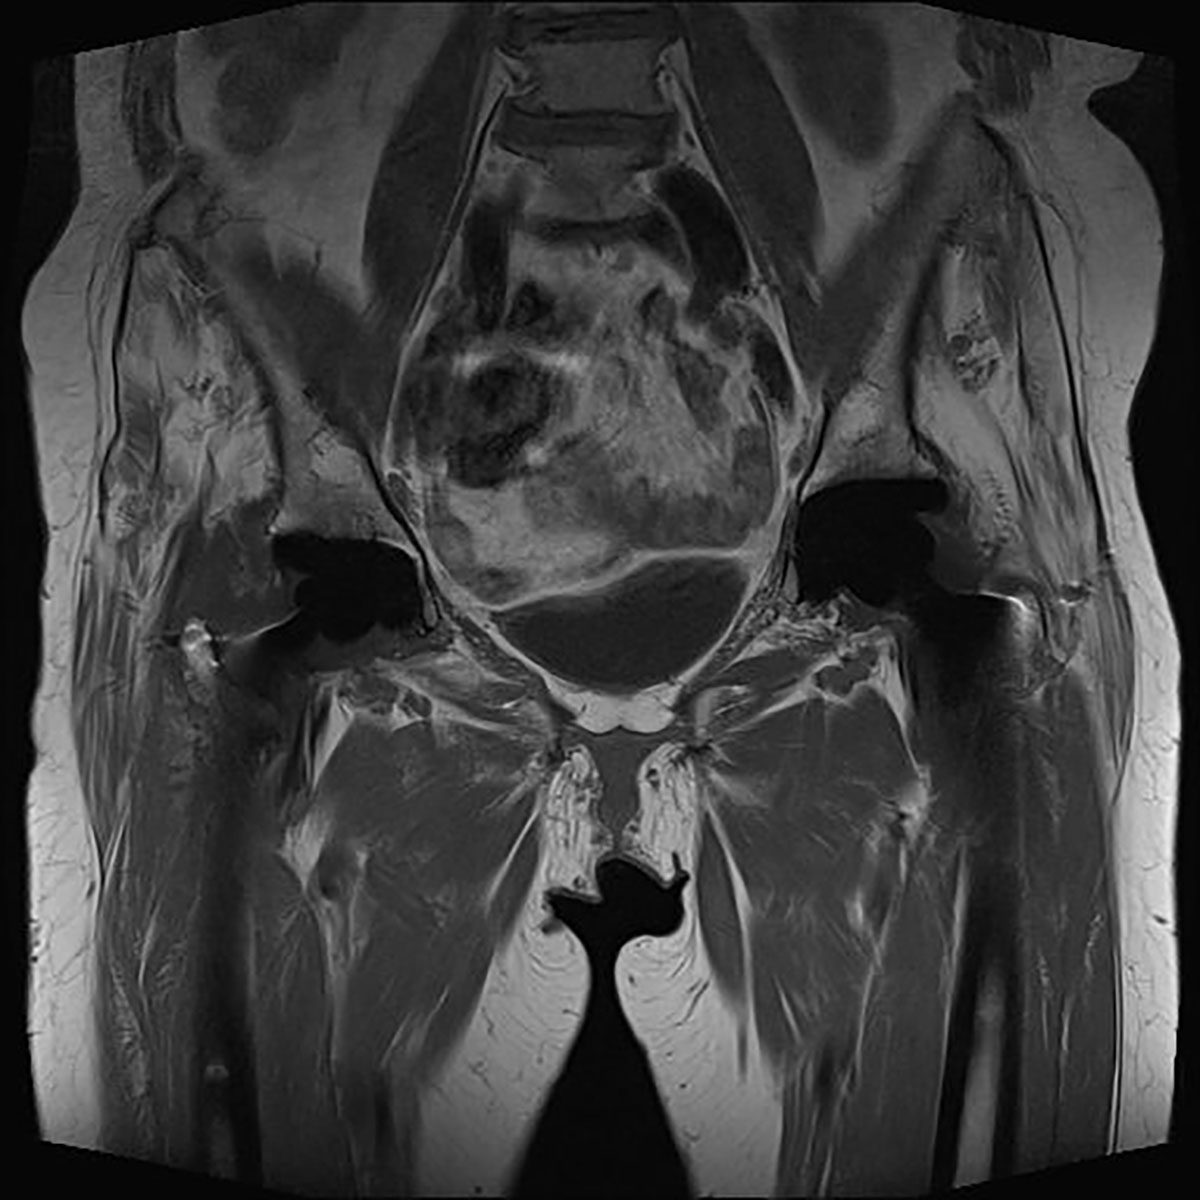

Neben einer typischen Anamnese und klinischen Untersuchung stellt die Bildgebung das entscheidende diagnostische Mittel zum Nachweis einer glutealen Insuffizienz dar. Konventionelle Röntgenbilder (Hüftübersichtsaufnahme a.-p., axiale Projektion des proximalen Femurs, ggf. Faux-Profilaufnahme) dienen zum Ausschluss ossärer Differentialdiagnosen. Bei einliegender Hüft-TEP muss auf mechanische Ursachen wie Lockerung und Komponentenfehlpositionierungen (Drehzentrum der Pfanne, Femur-Offset, Komponentengröße) geachtet werden. Bei nativem Gelenk können peritrochantäre Sehnenansatzverkalkungen oder osteophytäre Ausziehungen als Ausdruck degenerativer Veränderungen erkannt werden. Sonographisch bietet sich die Möglichkeit, ansatznahe Rupturen zu beurteilen, die Sensitivität wird vereinzelt als gut beschrieben. Als Goldstandard gilt die MRT des Beckens. Hierbei gelingt es, durch Wahl geeigneter Sequenzen und Schichtungen Tendinopathien und Rupturen hoch sensitiv nachzuweisen. Bei einliegender Hüft-TEP sind zur genauen Beurteilung der Glutealmuskulatur artefaktreduzierte Sequenzen (z. B. MARS) nötig.